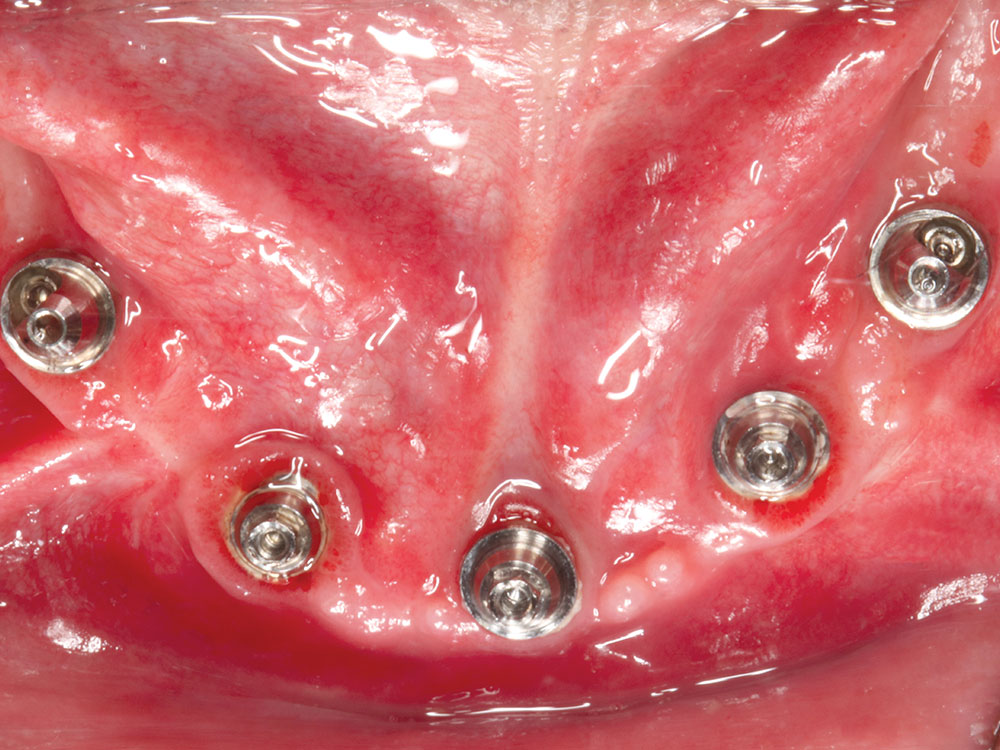

Dr. Fish recently placed five mandibular implants for a patient who requested a permanent solution for terminal dentition. He opted to place and immediately load five Hahn Tapered Implants with a fixed provisional denture. After the implant sites healed, Hahn Multi-Unit Abutments were connected to the implants and elevated the restorative platform above the soft tissue, thereby simplifying the fabrication of the immediate provisional denture as well as the final restoration.

Prior to the surgical appointment, we had a temporary denture specifically made for conversion to a fixed appliance after placing implants. We took out his remaining lower teeth and immediately placed five Hahn™ Tapered Implants (Glidewell; Irvine, Calif.). I positioned the three anterior implants axially, and I angled the posterior implants mesially to avoid the inferior alveolar canal. I freehanded the surgical procedure, and it came out really well. We connected three straight multi-unit abutments to the anterior implants and two angled 17-degree multi-unit abutments to the posterior implants. Then, we prepared holes in the denture, did the pickup procedure with the temporary cylinders, reshaped it, and sent him home with the fixed, converted denture in place. This was my first immediate load fixed full-arch restoration on multi-unit abutments. As I mentioned earlier, this was a procedure I learned at Dr. Patel’s course at Glidewell. It was something I took home with me and was able to put it into practice within a few weeks. The patient is kind of a quiet guy, but it was obvious that he was really happy to leave there with fixed teeth.

CM: We’ve actually made multi-unit abutments a standard part of our restorative protocol for the BruxZir Implant Prosthesis, whether the dentist loads the implants on the day of surgery or waits until the implant sites have healed. How has your experience been with multi-unit abutments?

JF: They help tremendously in these cases because it elevates everything above the gingival tissue. When you get the multi-unit abutments in place at the beginning of treatment, it makes the try-ins, the provisional and the delivery of the final restoration an easier experience for the dentist and the patient. This particular patient was something of a dental phobic, and we only had to sedate him once. After placing the implants and connecting the multi-unit abutments, each subsequent visit went smoothly because we could easily attach the try-ins and didn’t have to worry about impinging on his gingiva. So just from the patient’s standpoint, he would tell you that he doesn’t remember one bit of pain or discomfort through the whole procedure. It’s phenomenal.